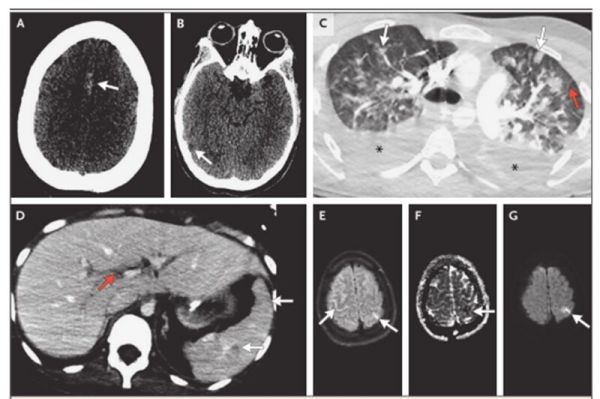

頭部 CT:雙側皮質溝內散在曲線狀高密度影,頂葉、顳葉局部低密度影,灰白質分界不清(圖 A、B)。

頭部 MRI:FLAIR 序列多灶性蛛網(wǎng)膜下腔溝高信號(圖 E、F、G)。

腹部和盆腔 CT:多個脾臟低密度區(qū),伴輕度腹水和輕度門脈周圍水腫。(圖 C、D)

CT 提示急性蛛網(wǎng)膜下腔出血、急性皮質梗死,MRI 多灶性蛛網(wǎng)膜下腔溝高信號,常見于蛛網(wǎng)膜下腔出血或急性腦膜炎。

CT 左側頂上葉、右側顳葉局部低密度影,在 MRI 上與限制性擴散相關,符合雙側急性皮質梗死。